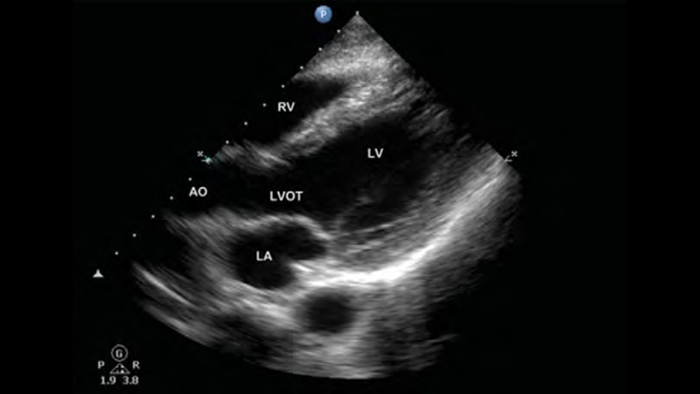

Broadband phased array transducer

Lumify S4-1 broadband phased array transducer

• 4 to 1 MHz extended operating frequency range

• 2D, color Doppler, M-mode, advanced XRES and multivariate harmonic imaging

• High-resolution imaging for abdominal and cardiac applications: Cardiac, OB/GYN, Lung, Abdomen and FAST imaging preset optimizations